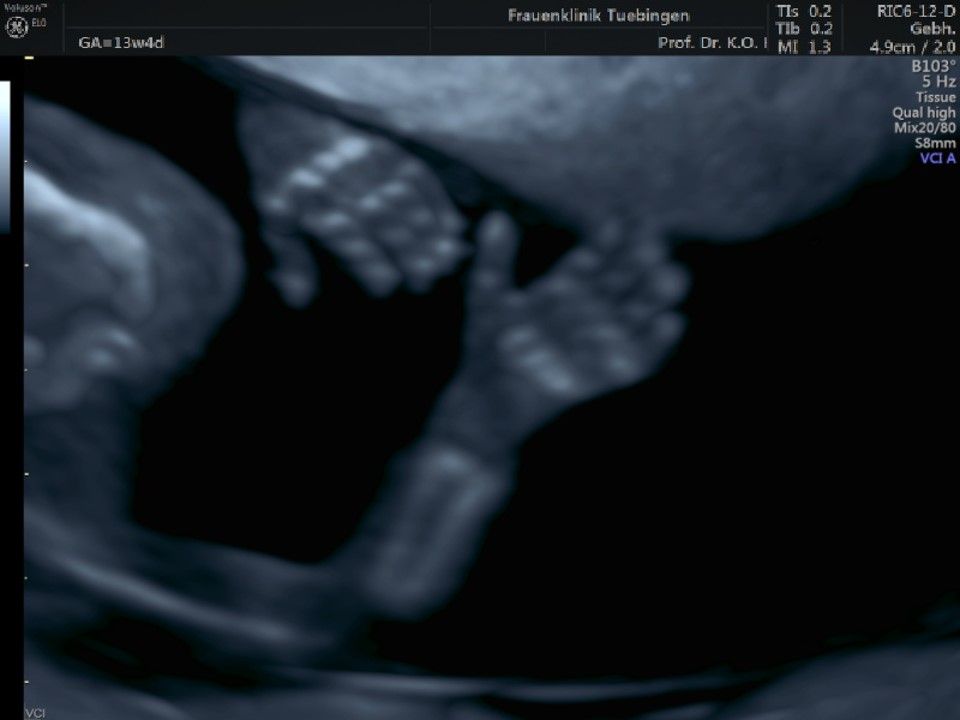

Im Rahmen des Ersttrimester-Screenings untersuchen wir die Organe des Feten mittels Ultraschall. Dabei machen wir auch gerne ein Bild für Sie.

Obwohl der Fet zu diesem Zeitpunkt erst zwischen 5 und 8cm groß ist, lassen sich bereits etwa die Hälfte aller schwerwiegenden Fehlbildungen erkennen bzw. ausschließen. Sollten wir eine Auffälligkeit sehen, werden wir mit Ihnen den Befund und das weitere Vorgehen ausführlich besprechen.

Die eigentliche Organuntersuchung findet um die 20.SSW (zweites Screening) statt. Das Ersttrimester-Screening und das zweite Screening sind sich ergänzende Untersuchungen und ersetzen sich gegenseitig nicht.